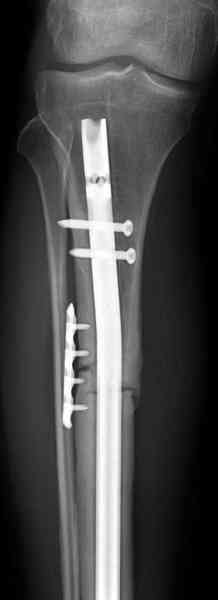

Оперирован в военном госпитале с заменой сегмента аллокостью

большеберцовой кости и после демобилизации явился для постоянного

наблюдения по месту жительства.

Наши имели проблему со сращением, пришлось им сделать динамизацию,

дополнительную аутопластику.

Снимки представлены.

Имя     : 3 adamantioma ap prox plate.jpg